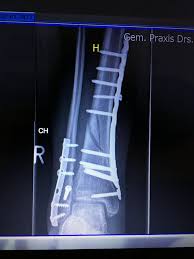

Fraktur oberhalb der verletzen Syndesmose Membrana interossea häufig auch rupturiert Die Maisonneuve-Fraktur wird als Sonderform der Sprunggelenksfraktur auch als Weber C klassifiziert. This normally takes approximately 6 weeks to heal. Die Weber-Klassifikation eine Methode zur Beschreibung von Sprunggelenksfrakturen.

KLASIFIKASI FRAKTUR WEBER Drsimon ponco septiono f Weber A Garis fraktur berada dibawah syndemiosis thibiofibularis f Weber B Garis fraktur berada setinggi syndemiosis thibiofibularis f Weber C Garis fraktur berada diatas syndemiosis thibiofibularis f. Weber C Fraktur immer Weber A- und Weber B- Frakturen mit. Many translated example sentences containing Weber c Fraktur English-German dictionary and search engine for English translations.

Weber C Fraktur. Neben der Weber C Fraktur gibt es auch noch die Fraktur der Klasse A und B. Was ist eine Weber-C-Fraktur. DayZ sa well kit DayZ Expansion Building Kits - YouTub. Verschobenem Bruch dislozierte Fraktur undoder. It has a role in determining treatment. Weber C Fraktur. Look up the French to German translation of weber c fraktur in the PONS online dictionary. The Weber ankle fracture classification or Danis-Weber classification is a simple system for classification of lateral malleolar fractures relating to the level of the fracture in relation to the ankle joint specifically the distal tibiofibular syndesmosis.